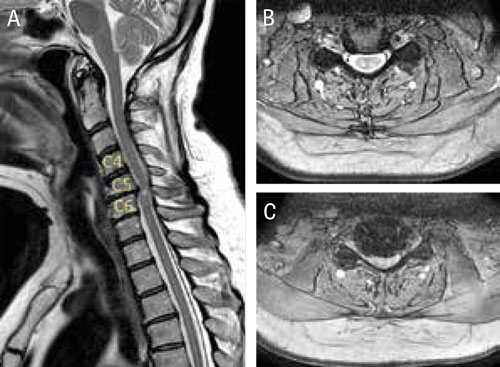

A) Patient med central stenos i cervikalryggen med uppklarning i ryggmärgen i nivå C 5–C 6: axialsnitt från B) C 4–C 5- respektive C) C 5–C 6-nivåerna. Notera att inget likvorskikt ses runt ryggmärgen i nivå C 5–C 6.